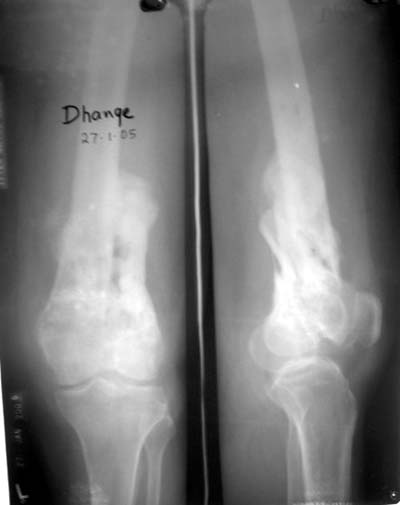

Качественные только исходные рентгенограммы (вышлю или завтра или в понедельник). Все последующие рентгенисследования были малоинформативны

(в т.ч. и последние снимки). КТ-исследование делалось 3 или 4 дня назад...

This is a coronal split in the femoral condyle and is a rare injury. Please see attachment for ORIF result

CT shows major bony fragments which are markedly rotated .With this amount of bony damage,you probably should attempt to get reasonably loooking knee with ORIF and thn if he needs a TKR due to pain a few years from now, then tleast you have something looking like a knee that you can replace rather than having to use revision knee for a primary TKR now. 4 weeks is not too long .what is the condition of soft tissues?

Before the CT and MRI era, we were treating the fractures with study of the Xrays alone. Such fractures with skeletal traction followed by non wtbearing mobilisation used to yield a fairly good range of movements. The CT gives a real ghastly picture of not so bad looking plain Xrays. I think this case needs traction to start with to correct the flexion deformity which probably will be achieved in 2 weeks time or less. We can then reassess the case with fresh Xrays. If possible one should try and fix the fragments to get some alignment. But the fixation should be stable enough to be able to mobilise the joint. Otherwise the traction can be continued for another 2 weeks to make the fracture sticky and then mobilise. We could get about 70 to 80* movements in spite of such communition. I am enclosing an Xray of a patient who is walking independantly and has 0 to 80* movemnts of the knee for the last one year

Фронтальные внутрисуставные переломы мыщельков бедра, так называемые Hoffa fracture, не частые, но встречающиеся переломы, в основном они связаны с травмой высокой энергией.